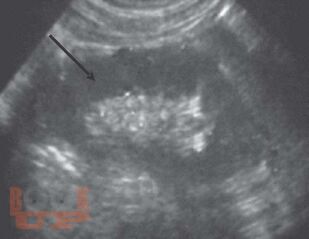

Монография посвящена применению лучевых методов исследования в ранней диагностике острого пиелонефрита. Систематизированы лучевые симптомы заболевания, на основании применения рентгенологического и ультрасонографического методов, а также метода компьютерной томографии. Представлена лучевая семиотика различных форм гнойного пиелонефрита (апостематоз, карбункул, абсцесс). Показана динамика изменений воспалительного процесса в паренхиме почек в процессе лечения. Данное практическое руководство будет интересно врачам лучевым диагностам, терапевтам, урологам, хирургам, а также студентам медицинских вузов.